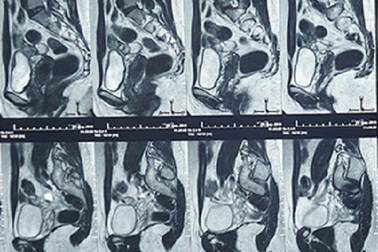

15 năm rong kinh, đau vùng chậu vì lạc nội mạc tử cungNhập viện trong tình trạng rong kinh kéo dài, đau vùng chậu đã điều trị nội khoa nhưng không khỏi, nữ bệnh nhân được bác sĩ chẩn đoán lạc nội mạc tử cung. Trước tình trạng u nội mạc tử cung xâm lấn nhiều nơi, bác sĩ đã phải phẫu thuật triệt để cho người bệnh.